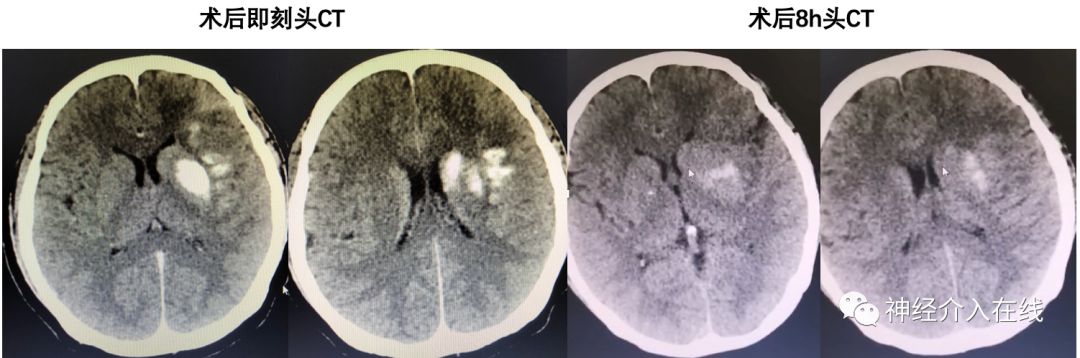

术后患者躁动明显缓解,下肢远端肌力略有恢复,术后即刻复查头CT提示造影剂滞留,8h复查CT高密度影明显减少,嘱华法林钠继续抗凝,监测INR。

术后次日(2019-7-21):患者凝视消失,右侧肢体肌力III级,NIHSS降至9分。